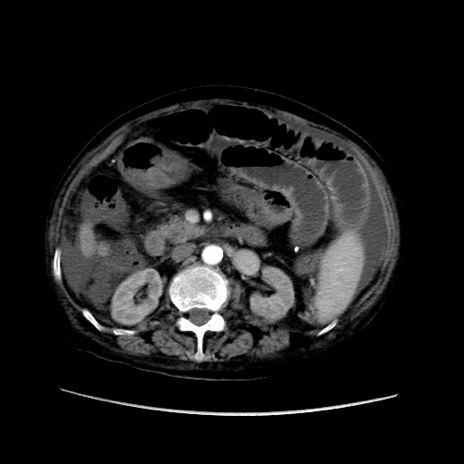

症例31(横断像)

【症例】80歳代 女性

【主訴】腹部膨満感

【現病歴】他院にて肝硬変にてフォロー中。1週間前から便秘、腹部膨満感、臍部腫瘤あり受診となる。

【既往歴】肝硬変

【身体所見】腹部膨隆あり、皮膚変化なし、疼痛なし。

【データ】WBC 4600、CRP 0.25